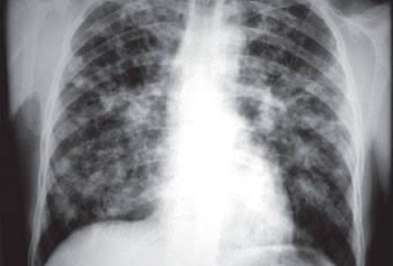

Briefly highlighting some unseen evidence of two comorbid COVID-19 patients

Abdullah, Muhammad Salman, Sher Ali, Riaz Muhammad, Aiman Waheed, Muddasir Khan, Sana Ullah, Carlos Augusto Fernandes de Oliveira